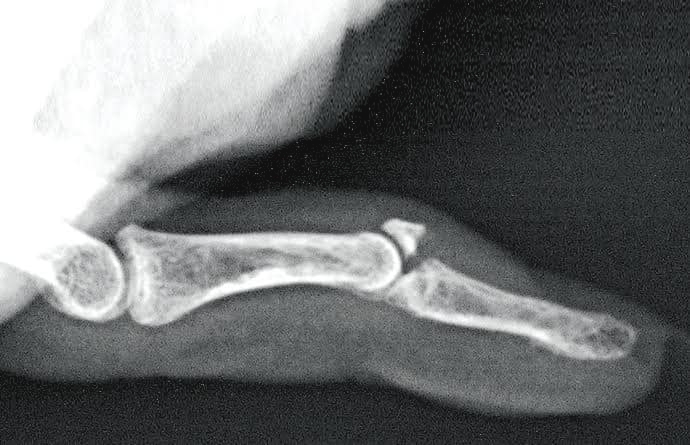

(圖一) 槌狀指手指末端呈下垂的狀態 (圖二)槌狀指可分為肌腱斷裂或尾指骨折 槌狀指患者手指最尾一節通常呈向下垂的形態(圖一),怎樣用力也不能伸直。這是因為負責伸直手指的肌腱(俗稱筋)不能把最尾一節拉起,主要原因為:1. 末端指關節骨頭沒有受傷,不過控制該關節伸展功能的肌腱斷裂。(圖二)2. 關節伸肌腱韌帶沒有受損,不過最尾一節指骨骨折。(圖二)以上兩種情況都會造成尾指骨關節功能的受損,以致出現受傷消腫之後最尾一節指骨不能伸直。病徵及診斷:

臨床檢查及X光(圖三)已足夠作出適當的診斷及制定之後的跟進治療

(圖三) X光可清晰看到手指有否骨折 (圖四) 手指固定托 手指固定托 (Finger Splint):患者若確定沒有骨折,便可佩戴特定的手指固定托(圖四)約6~8星期,是有很大機會復原,不過效果並非百分之百。佩戴手指固定托主要目的是要固定及伸直末端尾指關節,斷裂肌腱的兩端有機會靠近而結迦(Scar formation)並自行癒合。若要達到理想的效果,者務必遵從醫生或物理治療師的建議,必需6-8星期內連續24小時無時無刻都穿戴著,不論進食、工作、洗手、洗澡、睡覺等,都不可以除下來,否則時戴時不戴,受傷的關節一直處於活動狀態,肌腱斷裂的兩端就無法穩定靠近癒合,預後便不會理想。筆者到現在已無間斷地佩戴了超過4星期,只要耐心地等到受傷後6星期,便可除下手指托檢查一下肌腱的愈合情況,倘若愈合理想,便可減少每日佩戴的時間(只在晚上睡覺時佩戴),並開始進行一系列的物理治療去改善關節活動能力及幅度,並輔以針對性訓練去增加肌腱的強度。筆者過往也診治過不少因為球類運動「篤魚蛋」的患者,有部份患者輕看了病情而沒有即時求醫或只自行敷藥,到受傷2-3個月後,發覺手指末端仍然處於下垂的狀態及不能伸直,那時已錯過了佩戴手指托的黃金治療時間,此時就只有透過手術治療才能解決尾指下垂的情況。參考文獻:1. de Jong JP, Nguyen JT, Sonnema AJ, Nguyen EC, Amadio PC, Moran SL. The incidence of acute traumatic tendon injuries in the hand and wrist: a 10-year population-based study. Clinics in orthopedic surgery. 2014 Jun 1;6(2):196-202. -